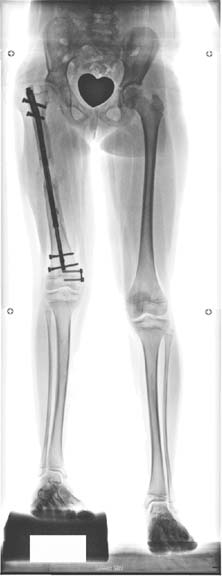

术前前后位和侧位X光片 (B) 使用10.7毫米大转子入路PRECICE 1胫骨钉进行6.5厘米延长后的前后位和侧位X光片(我们使用了胫骨钉,因为在当时大转子入路股骨钉尚不可用;目前的P2胫骨钉磁铁较短,不适合使用,但P1胫骨钉具有常规长度的磁铁,可用于股骨)。这是我们在2011年12月完成的首例PRECICE手术。(C) 6.5厘米延长后显示加重的外翻畸形的前后位X光片。(D) 通过内侧闭合楔形截骨术并使用锁定钢板内固定对畸形进行急性矫正后的前后位和侧位X光片。同时行腓神经减压术以尽量减少神经牵拉损伤的风险。(E) 一年后所有植入物取出后的最终前后位和侧位X光片。)